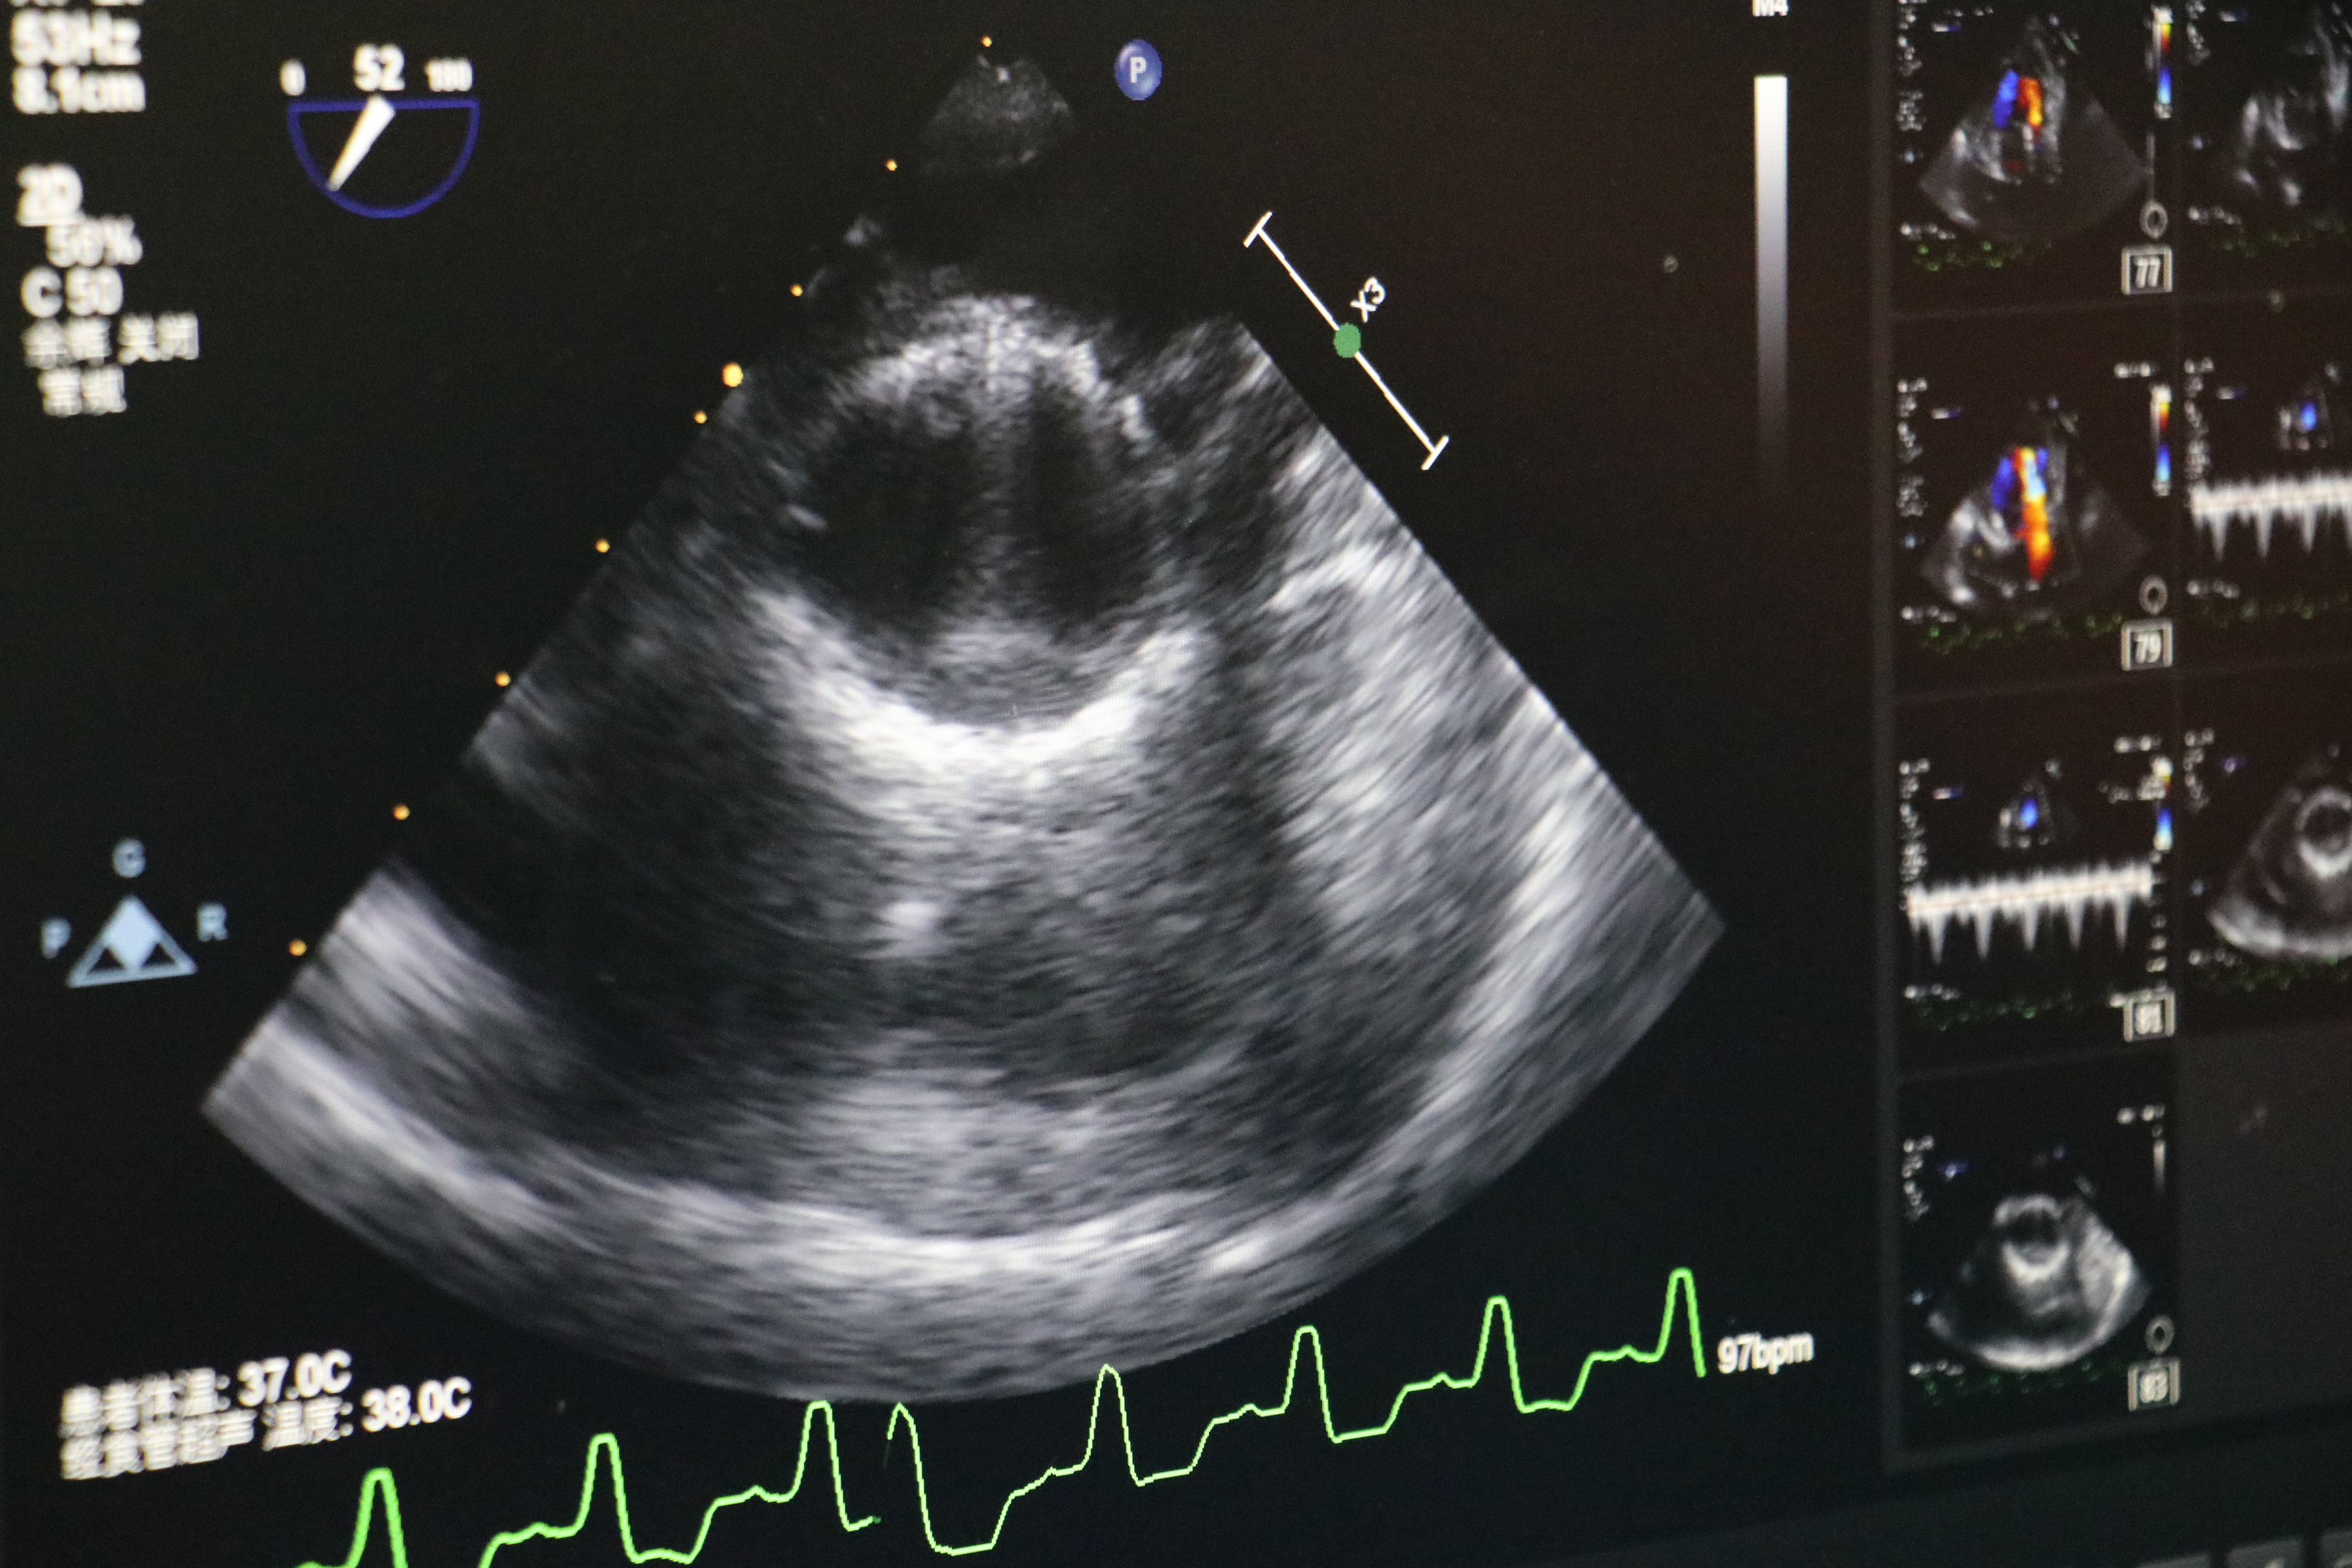

食道超声所示术中人工心脏瓣膜

再次造影及TEE发现:主动脉瓣无返流,介入瓣膜形态满意,无瓣周漏,无跨瓣压差。